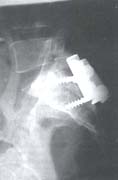

Se manejó en un primer tiempo quirúrgico, mediante abordaje posterior por línea media de columna lumbosacra y fijación con barras iliosacras más tornillos sacros; en un segundo tiempo quirúrgico por abordaje anterior y (lumbotomía) se realizó drenaje, curetaje y artrodesis de la articulación (figuras 7A – 7B – 7C – 7D – 7E.

Fig. 7C Aspecto transoperatorio del abordaje por línea media sacra y fijación con barras iliosacras más tornillos sacros.

Fig. 7D Vista radiográfica lateral de la técnica.